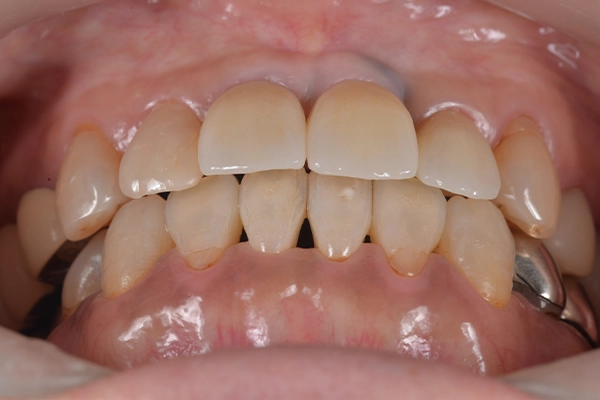

治療前後の比較

正面

before

after

治療前の正面から見た様子です。

矯正後、歯の先端のラインを整えることができました。